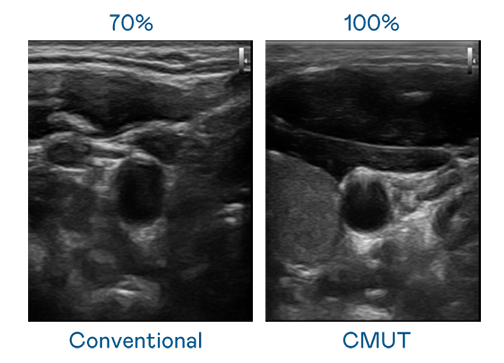

CMUT 技术是一种用电容式微机电元件来产生超音波讯号的技术。与传统 PZT 压电式技术相比,CMUT 频宽增加 30%,更宽频的超音波讯号让影像解析度大幅提升,是实现高影像品质医疗超音波扫描、促进精准医疗发展的关键技术。

大频宽带来超清晰影像

超音波影像的解析度高低,首先取决于探头能发出的讯号频宽。wepoker微扑克 CMUT 可提供高清晰的超音波讯号,提供高频宽、高灵敏度、影像纹理细节更高的超音波影像,协助医护人员缩短影像判读时间及利用精准的医疗影像进行诊断。